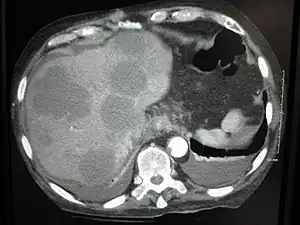

Cut surface of a liver showing multiple paler metastatic nodules originating from pancreatic cancer

Initially, nearby lymph nodes are struck early.[9] The lungs, liver, brain, and bones are the most common metastasis locations from solid tumors.[9]